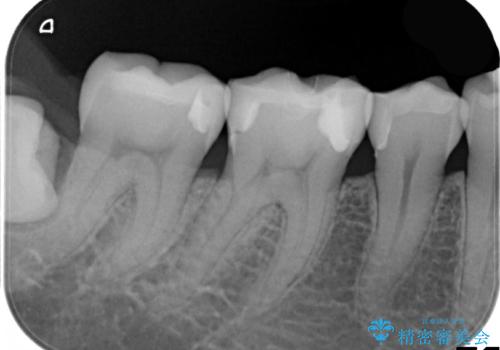

- 右下の奥の歯と歯の間に食べ物がつまること、つまったものがなかなか取れないことを主訴に来院されました。

右下6,7間に隙間があり、つめものの境目から虫歯になっていました。

セラミック希望とのことで、手前の歯も一緒に金属を外してセラミックにて修復することになりました。

セラミックでより自然な色合いに、かつ歯の形を修正することで物のつまりやすさを改善することもでき、大変満足していただけました。